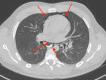

A Case of Spontaneous Pneumomediastinum Following Ecstasy and Marijuana Use

Spontaneous pneumomediastinum (SPM) is a benign and self-limiting condition more commonly seen in young adults. Radiology imaging of the chest, including X-ray or CT scan, is the gold standard for diagnosis. Ecstasy, also known as 3,4-methylenedioxymethamphetamine (MDMA) is a synthetic amphetamine derivative widely abused for an increased sense of well-being and euphoria. Marijuana is also abused for recreational purposes. SPM has been reported after both Ecstasy and marijuana use. SPM after these illicit drugs abuse usually has a benign and self-limiting course with supportive management. However, it is always important to rule out serious associated conditions like esophageal perforation. Here, we present a 22-year-old male who developed SPM after Ecstasy ingestion and marijuana inhalation.